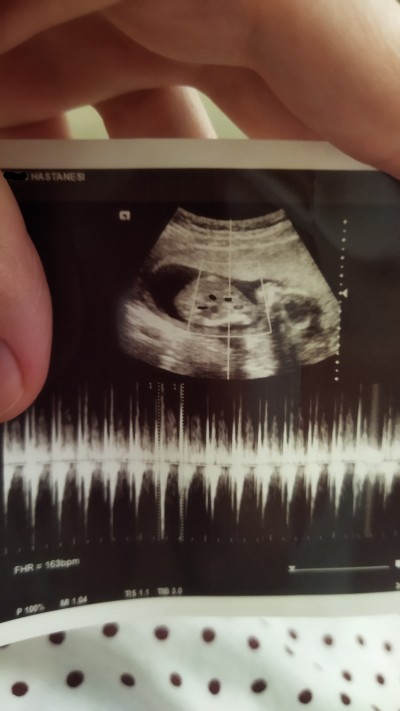

Cnsyetne bakablrmsnz

15 haftalık

15 haftalk

Kız gibi geldi bana Allah gönlüne göre versin

Doktor kız veya erkek dedi mi canım bende 15 haftalık hamileyim erken mi acaba daha cinsiyeti için diye düşünüyorum belli oluyor mu

Evet canım erkek dedi doktor. Merak ediyorum cinsiyet yanılması olabilir mi diye